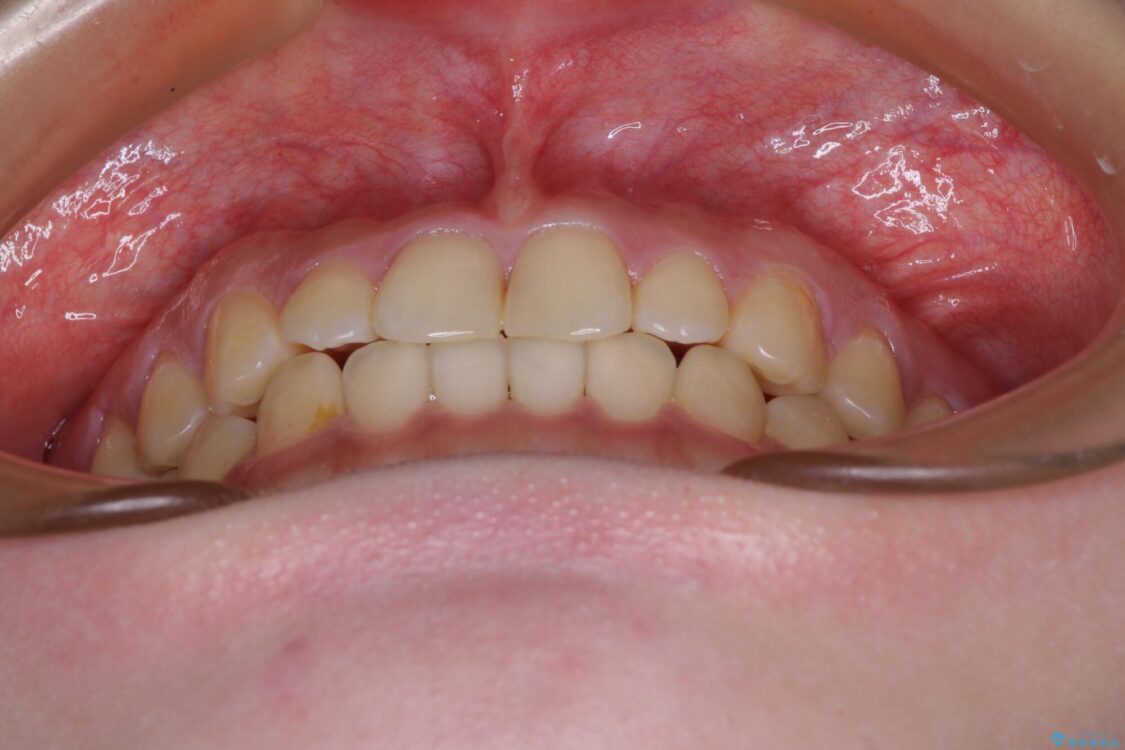

治療後

• 治療途中の奥歯と矯正治療の後戻り インビザライン・ライトによる矯正治療 治療後画像